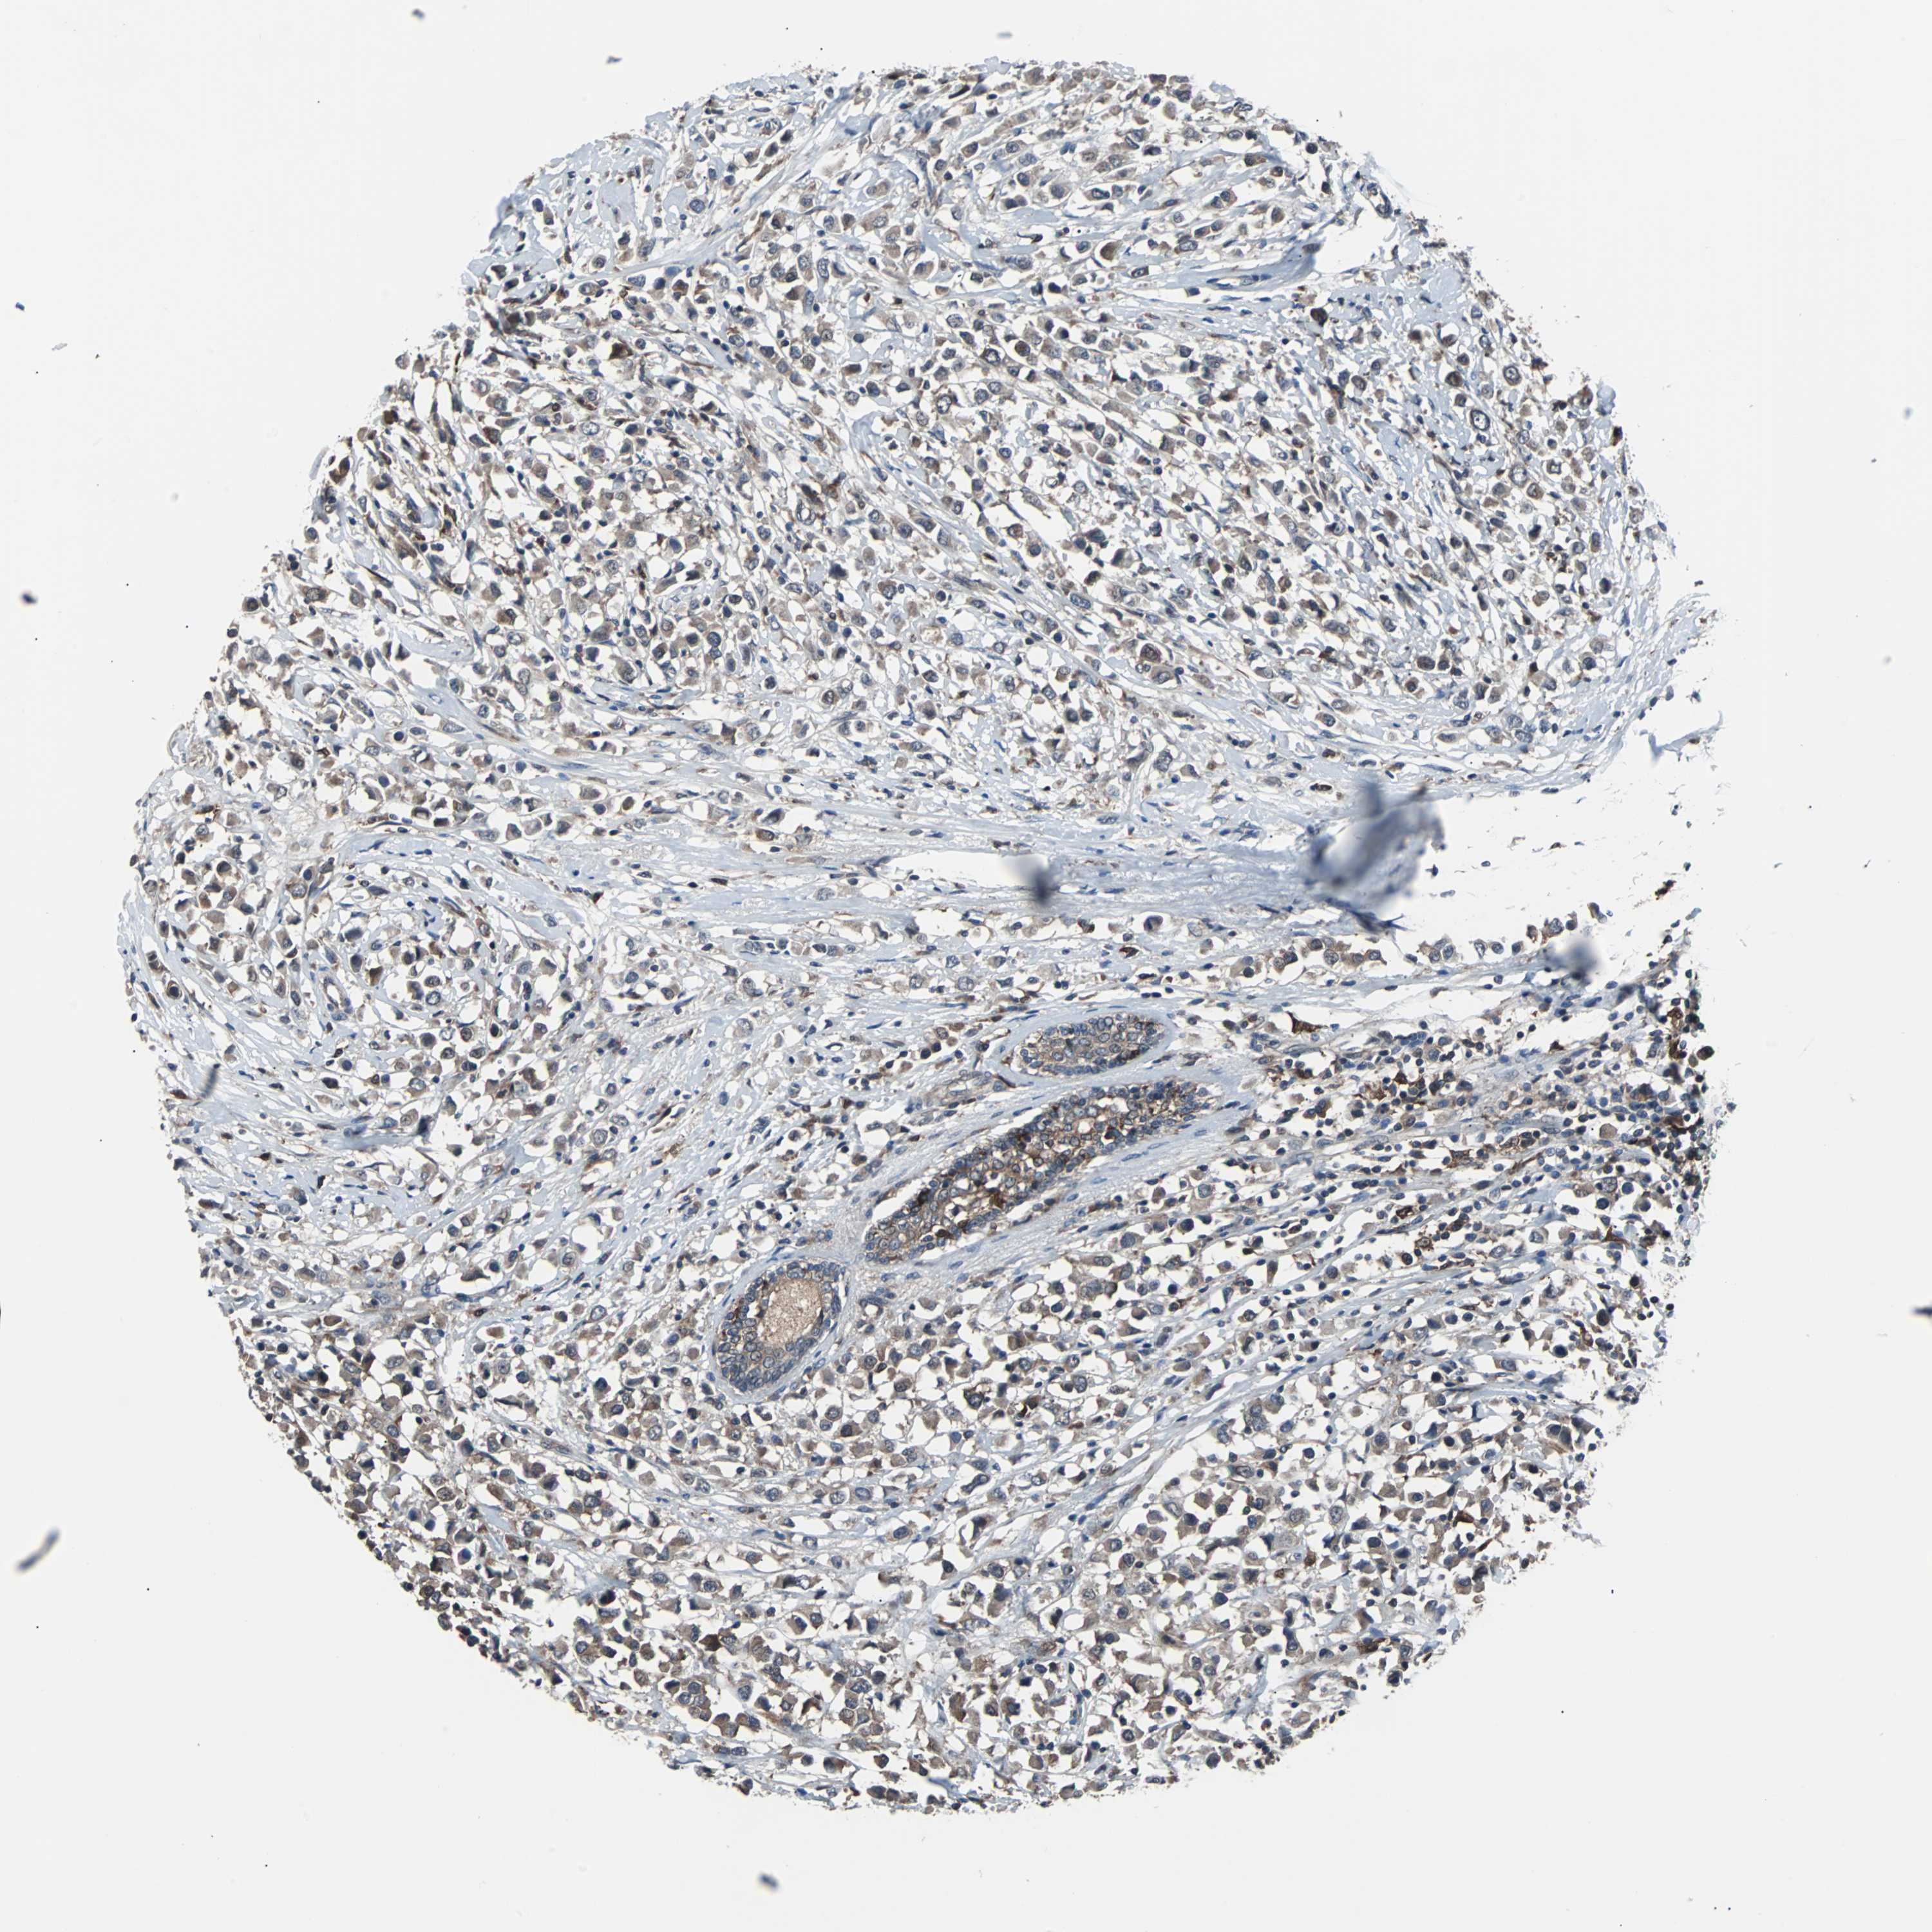

BRCA TCGA BRCA VALIDATION PROTEIN EXPRESSION

ANTIBODIES

AND

VALIDATION